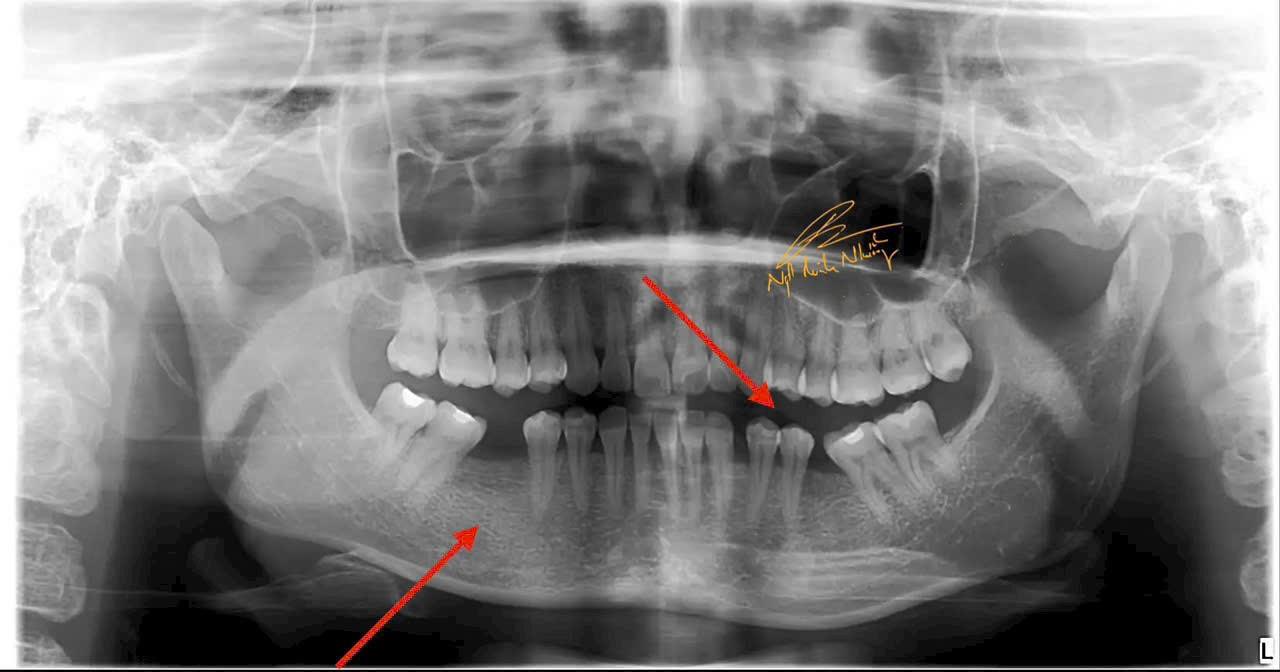

Teo xương hàm : Khi mất răng, xương hàm không còn được kích thích bởi các lực nhai, dẫn đến việc mất dần chất lượng và khối lượng xương tại khu vực mất răng. Điều này có thể làm thay đổi khuôn mặt và làm giảm khả năng lắp răng giả hoặc cấy ghép sau này.

Di chuyển các răng còn lại : Khi mất răng, các răng còn lại có thể bị xô lệch, làm thay đổi cấu trúc của hàm và gây ra các vấn đề về khớp cắn.